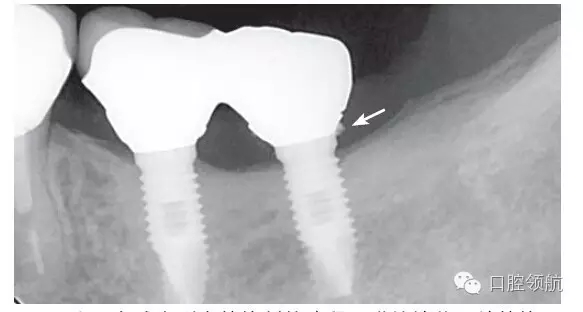

本病例,患者主訴是因為上部修復體脫落,來院檢查。使用臨時粘接劑,剩余部分的粘接劑在硬化前,盡量沖洗干凈。但在遠中范圍,可看到還有剩余的粘接劑,原因是將上部修復體戴入到制作的個性化基臺上,沒能調(diào)整粘接劑的用量,粘接劑被擠壓進入到齦下部位(圖4)。

圖4 為盡力減少剩余粘接劑的殘留,謹慎地戴入并粘接,但在遠中鄰面,仍可見到殘留的粘接劑。

使用多種配件的螺絲固位的修復方式,必須有高精度的技工技術,使用多種基臺配件,高精度的制作,技工的加工費用等會帶來較高的經(jīng)濟負擔,但這是臨床上無法回避的問題。一方面,期待“粘接”材料和技術的進步;另一方面期待金屬和瓷能有長期穩(wěn)定的結(jié)合效果?,F(xiàn)在,介紹一種先將上部基臺和上部修復體粘接固位后,再用螺絲固位的方法(圖5)。

圖5 氧化鋯基臺和氧化鋯冠用粘接劑固位,粘固形成一個整體后,再用螺絲固位,這樣比較起來,剩余粘接劑的問題得以解決,但螺絲孔產(chǎn)生的美學問題也出現(xiàn)了。使用氧化鋯材料大致能解決此問題。